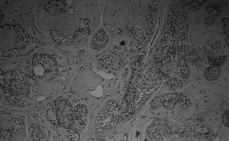

El estudio anatomo-patológico de la pieza se informa como carcinoma intraductal desarrollado en el seno de un fibroadenoma (Fig. 1); bordes quirúrgicos libres.

Figura 1. Fibroadenoma con focos de carcinoma in situ.